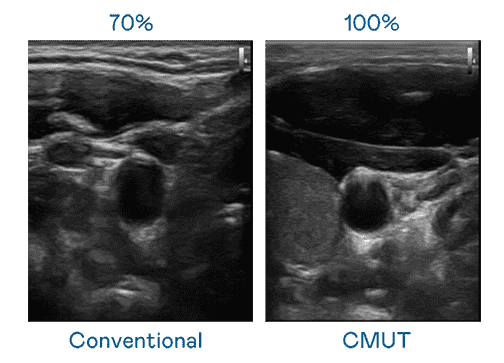

CMUT 技术是一种用电容式微机电元件来产生超音波讯号的技术。。。与传统 PZT 压电式技术相比,,CMUT 频宽增加 30%,,,,更宽频的超音波讯号让影像解析度大幅提升,,,,是实现高影像品质医疗超音波扫描、、、、促进精准医疗发展的关键技术。。。

大频宽带来超清晰影像

超音波影像的解析度高低,,,首先取决于探头能发出的讯号频宽。。。传奇国际 CMUT 可提供高清晰的超音波讯号,,,提供高频宽、、、高灵敏度、、、、影像纹理细节更高的超音波影像,,协助医护人员缩短影像判读时间及利用精准的医疗影像进行诊断。。